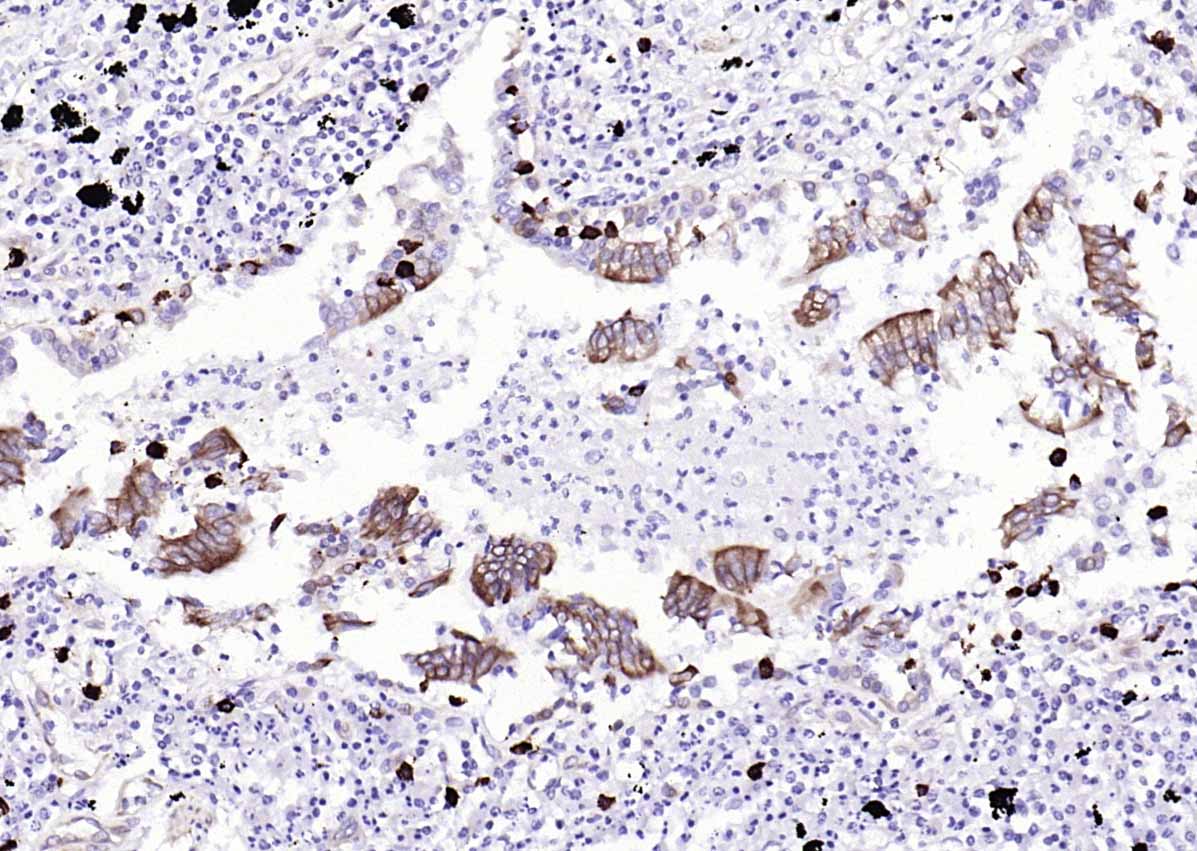

Paraformaldehyde-fixed, paraffin embedded (human lung carcinoma); Antigen retrieval by boiling in sodium citrate buffer (pH6.0) for 15min; Block endogenous peroxidase by 3% hydrogen peroxide for 20 minutes; Blocking buffer (normal goat serum) at 37°C for 30min; Antibody incubation with (STING1) Monoclonal Antibody, Unconjugated (bsm-60326R) at 1:200 overnight at 4°C, followed by operating according to SP Kit(Rabbit) (sp-0023)instructionsand DAB staining.